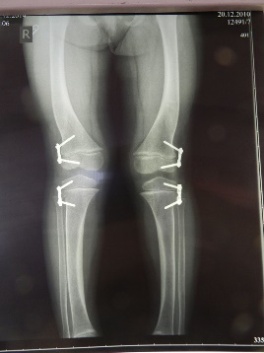

В норме бедро и голень во фронтальной плоскости чаще находятся под небольшим углом, открытым наружу до 174°, то есть, имеется физиологический вальгум. При патологии коленного сустава это соотношение нарушается, угол либо увеличивается, либо уменьшается, колено при осмотре спереди может быть отклонено внутрь или наружу.

У практически здоровых людей возможна двусторонняя вальгусная деформация коленных суставов, при осмотре спереди ноги напоминают букву «X» (иксобразное искривление). Причиной такой деформации могут быть перенесенные ранний или поздний рахит, длительные значительные физические нагрузки, злоупотребление спортом в подростковом возрасте, быстро нарастающая полнота у молодых женщин. Возможно «0»-образное (варусное) искривление ног.

При варусной и вальгусной деформациях коленных суставов наиболее эффективен гемиэпифизиодез - это временное блокирование зоны роста кости. Он не влияет на качество жизни ребенка, но при этом за несколько лет позволяет полностью восстановить правильную форму коленных суставов

Варусная и вальгусная деформации коленных суставов – это патология развития нижних конечностей, которая требуют своевременного лечения.

Варусная форма болезни протекает благоприятнее, чем вальгусная деформация, при которой коленные суставы искривляются на бок. Двустороннее поражение приводит к Х-образной форме ног. Варусная деформация сопровождается патологическим изменением формы голеней, которые приобретают О-образный вид. Это приводит к растяжению связок, повышению нагрузки на суставные ткани нижних конечностей, увеличению риска развития артроза, остеохондроза, плоскостопия.

При появлении первых признаков деформации коленных суставов необходимо обратиться к детскому травматологу-ортопеду. С помощью рентгенологических методов диагностики удается оценить состояние костной системы, определиться с дальнейшей тактикой лечения.

На первом приеме ортопед оценивает степень деформации коленных суставов, определяет форму заболевания, назначает комплексное обследование. После получения всей необходимой информации о состоянии здоровья ребенка врач подбирает дальнейшую схему лечения. Поставить точный диагноз и выявить варусную или вальгусную деформацию коленных суставов можно с помощью рентгенодиагностики.

До 4-х лет хирургические методы стараются не применять. По достижению этого возраста при неэффективности консервативных методик используют гемиэпифизиодез — хирургическую коррекцию, при которой проводят малоинвазивное временное блокирование зоны роста кости.

При варусной и вальгусной деформациях коленных суставов этот метод наиболее эффективен. Он не влияет на качество жизни ребенка, но при этом за несколько лет позволяет полностью восстановить правильную форму коленных суставов.